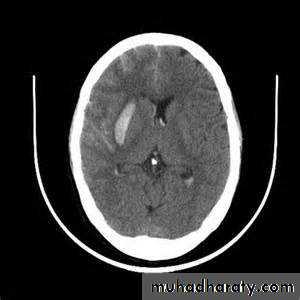

Hydrocephalus

Significant volume of intraventricular blood is a poor prognostic indicator.

The presence of hydrocephalus is associated with a poor outcome.